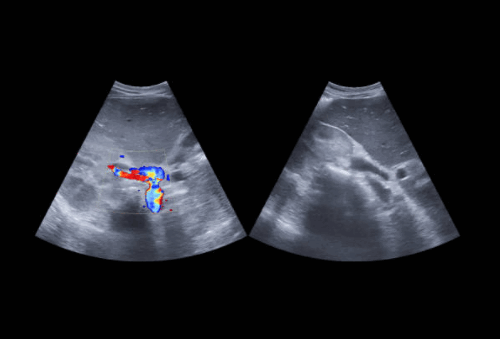

Гипоэхогенные регионы. В некоторых наклонных рекуррентных срезах на УЗИ желчный пузырь может давать вид округлого гипоэхогенного очага внутри паренхимы печени. Как только анатомия желчного пузыря становиться понятной, это не должно вызывать никаких проблем. Тем не менее, иногда, если есть сомнения, можно дать жирную пищу для сокращения желчного пузыря. Другие гипоэхогенные изображения в печени могут быть венозными. Возможно получить изображения поперечных срезов сосудов, которые имеют округлый вид и могут возникать из печеночных или портальных вен. Расширенные вены, особенно слияние средней и левой печеночных вен, могут также приводить к появлению кистозных поражений. Такая дилатация может встречаться даже при отсутствии стазиса. Различие между сосудами и кистозными поражениями легко сделать, изучая по УЗИ ход ветвление сосудов, а также их стенок или с помощью цветного ультразвукового допплера.

Гиперваскуляризированные метастазы в печени являются исключительным явлением, обычно возникающим из почечно-клеточного рака. Поэтому цветовой допплер редко бывает положительным при метастазах. Цветовой допплер более полезен при изучении взаимосвязей образований с ветвями сосудов печени.